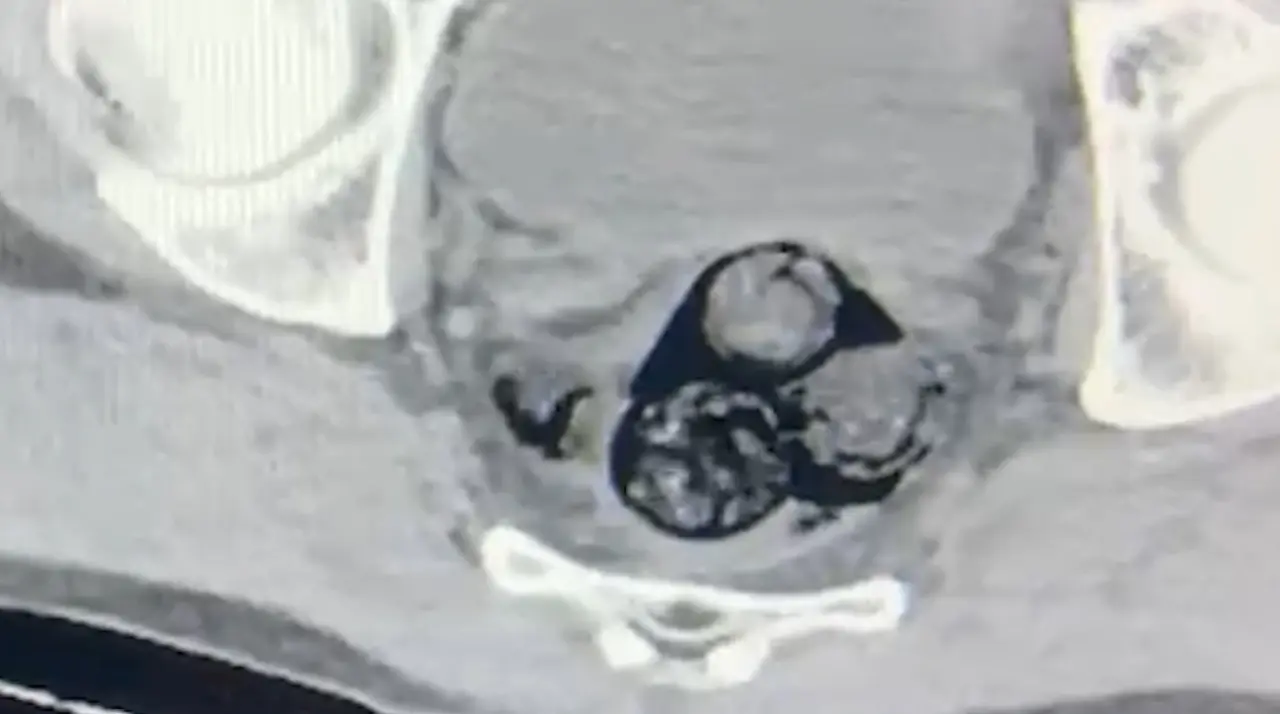

Iğdır İl Emniyet Müdürlüğü Narkotik Suçlarla Mücadele Şube Müdürlüğü ekipleri, yurt dışından Türkiye’ye giriş yapan ve şüpheli hareketler sergileyen A.İ. isimli kişiyi takibe aldı. Yapılan detaylı aramalar neticesinde, şahsın vücut boşluklarında uyuşturucu madde taşıdığı belirlendi. Radyolojik görüntüleme sonucu, şüphelinin makat bölgesinde dört farklı yabancı cisim olduğu ortaya çıktı. Sağlık kontrolünden geçirilerek, çıkarılan cisimlerin içinde toplamda 140 gram metamfetamin olduğu tespit edildi. Uyuşturucu madde taşımak ve ticaretini yapmak suçundan hakkında işlem başlatılan A.İ., Iğdır Adliyesi’ne sevk edildi. Mahkemeye çıkarılan şahıs, tutuklanarak cezaevine gönderildi.